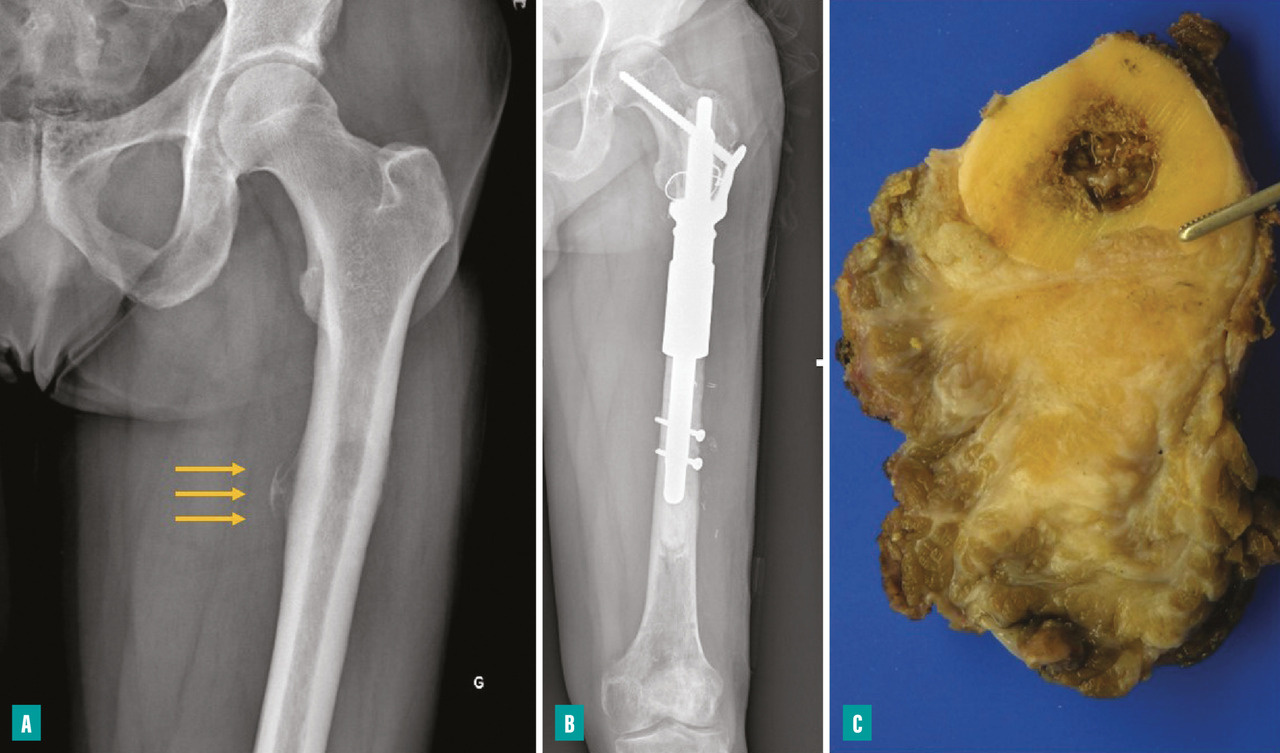

Pour les sarcomes des membres, la préservation de la fonction articulaire est le facteur déterminant. Dans la mesure du possible, les chirurgies avec préservation épiphysaire doivent être privilégiées (fig. 1). En cas d’atteinte épiphysaire, le choix de la technique opératoire dépend de la présence ou non d’un envahissement intra-articulaire, qui nécessite alors de recourir à une résection dite «  extra-articulaire  », techniquement plus exigeante (fig. 2). L’imagerie par résonance magnétique (IRM) a une place de choix pour identifier cette contamination articulaire.